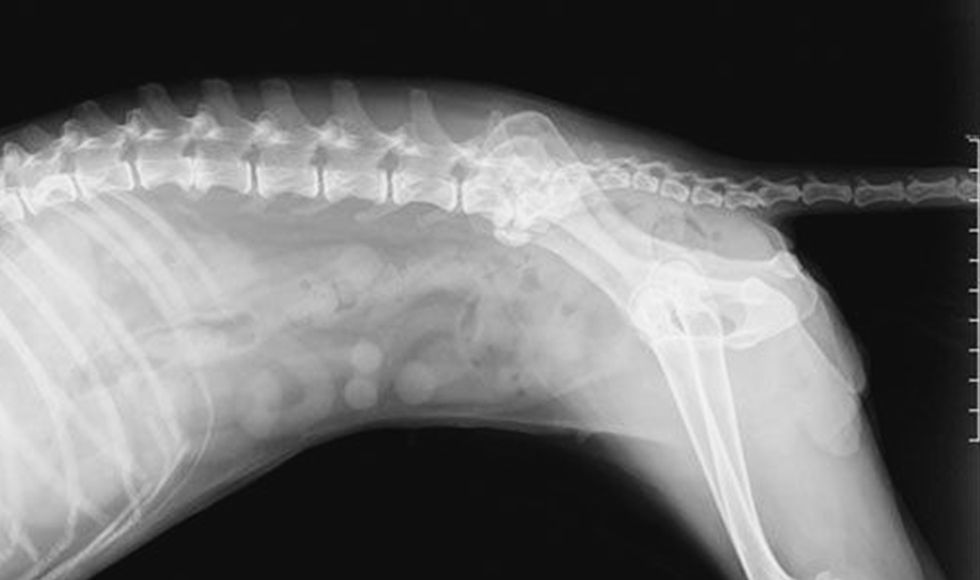

X-ray image of a dog's spine and hind leg.

Using digital radiographs, better known as digital x-rays, we can identify issues with broken or fractured bones, cancerous tumors, heart problems, gastrointestinal issues, kidney or bladder stones, and more. We’re proud to be able to provide advanced patient care with digital x-rays in Lake Charles.

When we take an x-ray of your pet to determine the cause of concerning signs of a medical condition, our digital equipment provides much better and more detailed images than older, non-digital models. This allows us to diagnose your pet faster and more accurately, leading to quicker treatment and, often, an easier recovery.